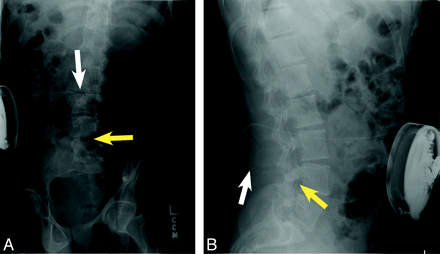

There is a paucity of evidence directly evaluating the ability of plain films alone to reliably identify pump- and catheter-related complications necessitating surgical revision. Nevertheless, several of the most common complications, including catheter-related problems such as kinking (Fig 4), migration, discontinuity (Fig 5), and other more obvious dislodgments, can often be identified by plain films. For this reason, plain radiography is typically the initial approach to imaging evaluation of suspected pump-catheter system malfunction. Information with respect to intrinsic pump function (eg, pump rotor/roller function) can also be obtained if radiographs are performed both before and after a programmed rotation of the rotor. An angular rotation of 90° or 120° is expected for the SynchroMed EL and SynchroMed II devices, respectively. Failure to observe rotor or roller movement usually indicates a rotor/roller malfunction, but occlusion of the catheter (eg, by a catheter kink) can also cause a rotor/roller stall. Exposure to an external magnetic field as with MR imaging can also affect rotor/roller motion (though the rotor should spontaneously restart once the magnetic field is removed).34

An AP radiograph demonstrates a kinked/folded catheter (yellow arrow) within the subcutaneous tissue.

AP (A) and lateral (B) radiographs demonstrating a discontinuous segment of the catheter, with broken catheter ends in the subcutaneous tissue of the lower back (white arrow) and the spinal canal (yellow arrow).

The combination of a standard abdominal radiograph, AP and lateral lumbar spine radiographs, and an AP thoracic spine radiograph usually fully visualizes the entire pump and catheter system,34 though proper imaging technique is crucial with respect to these plain radiographs to assess the entire subcutaneous course of the tunneled catheter. Plain films can be inconclusive, however, because simple anatomic visualization of the catheter and pump fails to provide information about catheter patency, occlusion,38 or leaks.